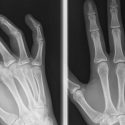

Sin embargo, la transición de la aleta a la extremidad no se produjo en una noche. El registro fósil indica que nuestros antepasados eran polidactilios, es decir, que significa que tenían más de cinco dedos, lo que plantea otra cuestión clave: ¿a través de qué mecanismo se produjo la evolución a la pentadactilia (cinco dedos) entre las especies actuales?

Al tratar de comprender la importancia de esta diferencia, Kherdjemil demostró que mediante la reproducción de la regulación igual a la del pez del gen hoxa11, los ratones desarrollaron hasta siete dígitos por pata, es decir, una vuelta al estado ancestral. El equipo de Kmita también descubrió la secuencia de ADN responsable de la transición entre la regulación como en los peces a la del ratón del gen hoxa11. «Esto sugiere que este importante cambio morfológico no se produjo a través de la adquisición de nuevos genes, sino simplemente modificando sus actividades», agrega Kmita.

Desde un punto de vista clínico, este descubrimiento refuerza la noción de que las malformaciones durante el desarrollo fetal no sólo se deben a mutaciones en los genes y puede proceder de mutaciones en secuencias de ADN conocidas como secuencias reguladoras. «En la actualidad, las limitaciones técnicas no permiten identificar este tipo de mutación en los pacientes directamente, de ahí la importancia de la investigación básica en modelos animales», concluye Kmita.